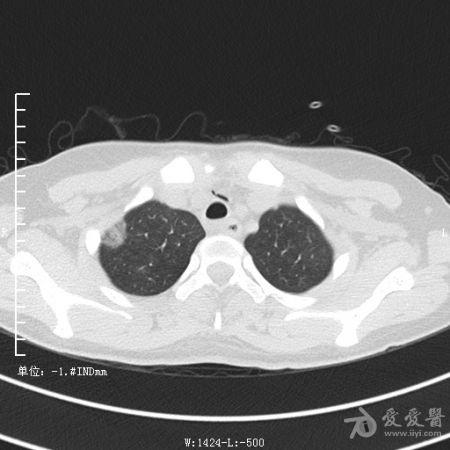

典型支气管扩张及肺水肿CT片

典型支气管扩张肺水肿